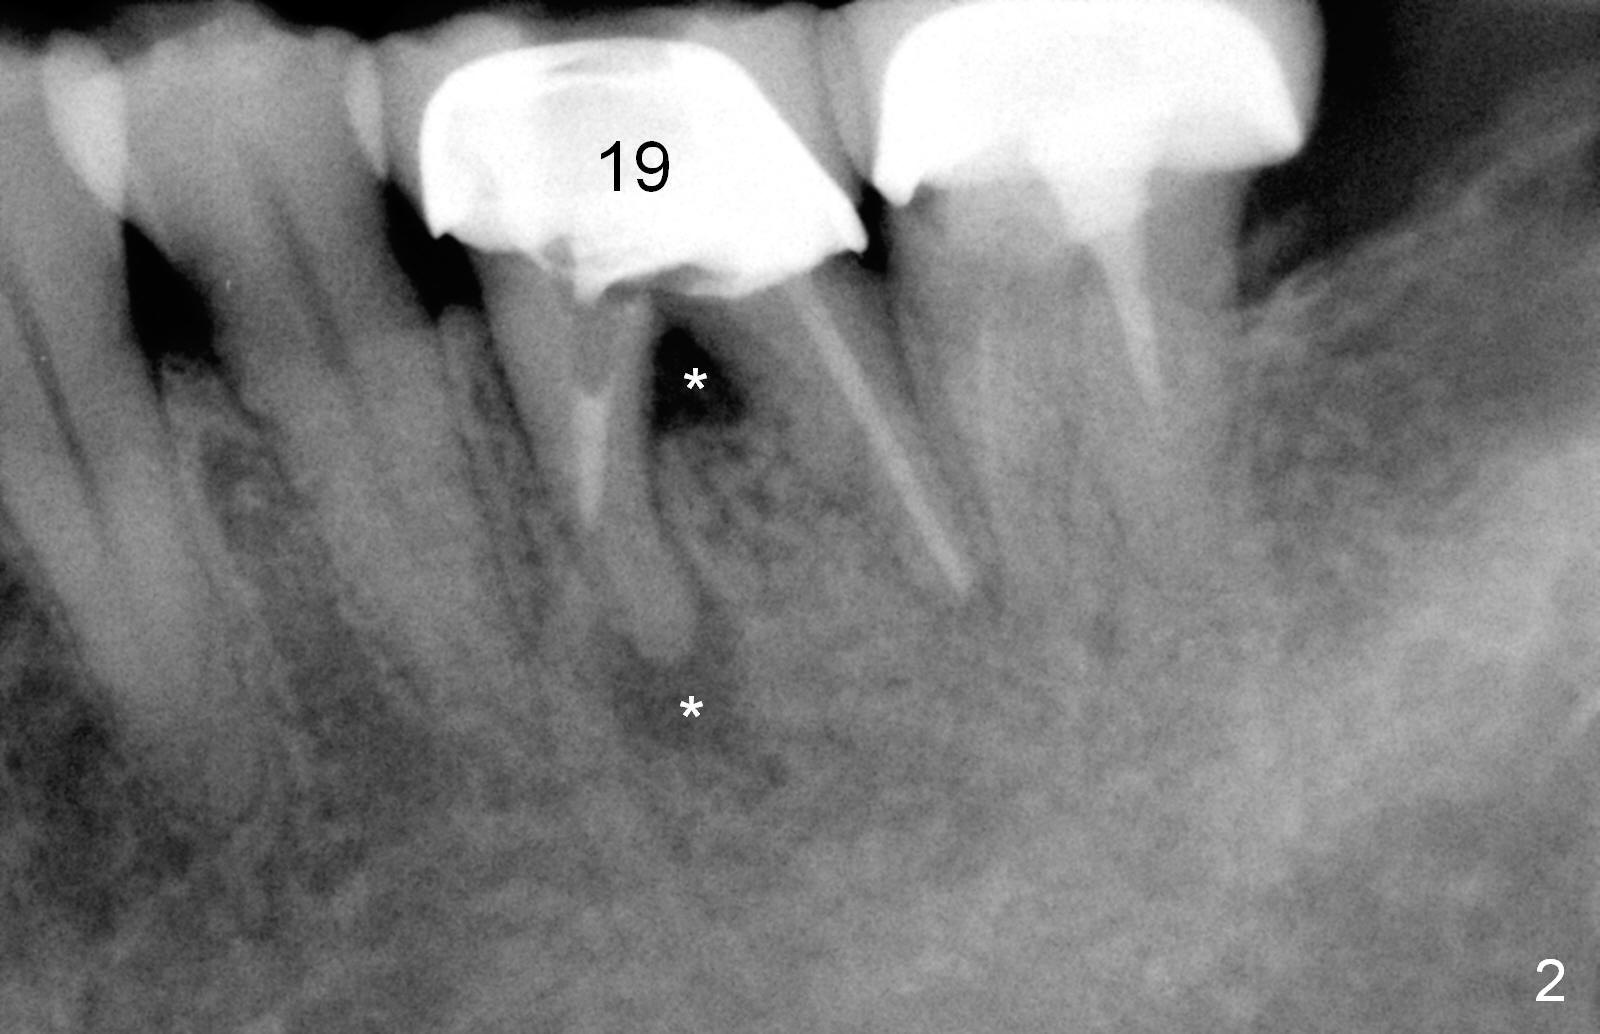

A 47-year-old lady lives out of town and presents to clinic with chief complaint "lower left back tooth easily bleeding with food impaction". Dental history and examination reveals failure of endo retreat of the tooth #19 (Fig.1), buccal gingival swelling (S), open access (A) and furcal and mesial periapical radiolucency (Fig.2 *). She is pleased to know availability of immediate implant and immediate provisional and accepts and receives the treatment at the same visit. The immediate implant (tissue-level) is designed to be as large as 7 mm and as long as 17 mm (Fig.3). To reduce paresthesia (yellow dashed line: the possible upper border of the Inferior Alveolar Canal)), a shorter implant (14 mm long in red line) is preferred. The tooth is extracted with sectioning. Granulation tissue is removed from the furca. The buccal plate appears to be intact. The septum is flat (Fig.4,10a S). Osteotomy starts in the middle of the septum with a 1.2 mm drill (Fig.10b red circle). As osteotomy increases in diameter (Fig.5 O), the apical end appears to be deviated mesiobuccally (Fig.10c large red circle). When a 6x17 mm tapered tap is being placed 14 mm deep (Fig.6 T), vibration of the buccal plate is seemingly felt at the apex (Fig.10d green circle). Further osteotomy may perforate the buccal plate. A 6x14 mm tissue-level implant is placed with >60 Ncm of insertion torque (Fig.7,8 I), followed by a 5x3 mm abutment (A) and bone graft (* in the remaining socket gap). An immediate provisional is cemented without occlusal contact (Fig.9 P).